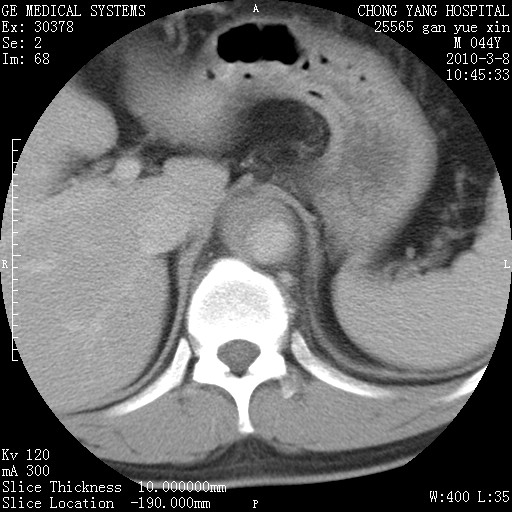

标题: CT24940:主动脉增强,典型病例。 [打印本页]

标题: CT24940:主动脉增强,典型病例。

夹层动脉瘤。

动脉夹层

夹层动脉瘤,典型

主动脉夹层。

动脉夹层的分型:

⒈debakey分型:根据主动脉夹层累及部位,分为三型:ⅰ型:原发破口位于升主动脉或主动脉弓部,夹层累及升主动脉、主动脉弓部、胸主动脉、腹主动脉大部或全部,少数可累及髂动脉。ⅱ型:原发破口位于升主动脉,夹层累及升主动脉,少数可累及部分主动脉弓。ⅲ型:原发破口位于左锁骨下动脉开口远端,根据夹层累及范围又分为ⅲa,ⅲb。ⅲa型:夹层累及胸主动脉。ⅲb型:夹层累及升主动脉、腹主动脉大部或全部。少数可累及髂动脉。

⒉stanford分型:a型:夹层累及升主动脉,无论远端范围如何。b型:夹层累及左锁骨下动脉开口以远的降主动脉。

夹层动脉瘤,少量胸水

夹层动脉瘤;左侧少量胸腔积液。

典型主动脉夹层。